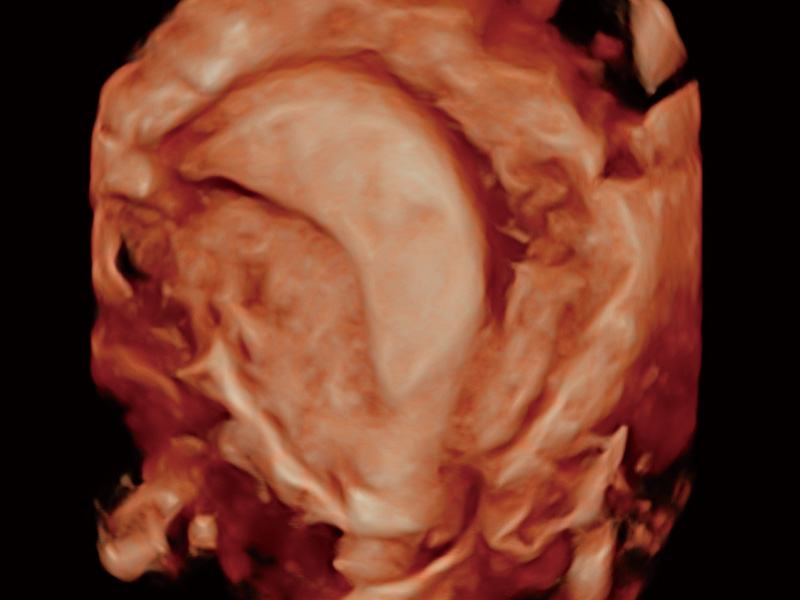

腔内容积探头

腔内三维成像技术获得显著提升,超大扇角在满足日常基础扫查的同时,支持卵泡自动测量及多种三维渲染模式,为您提供更多的诊断信息,尤其是在子宫畸形的诊断,内膜及肿瘤占位观测中起到了重要的作用。

单角子宫